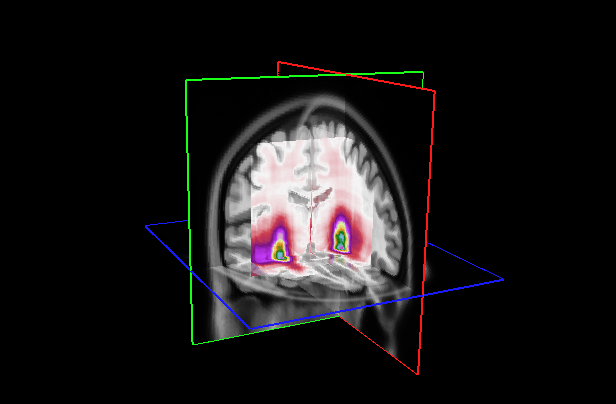

Refer to caption

Figure 7: (Left) Attention distribution for each plane averaged on all the five test to provide entire dataset distributions; (Right) Visualization of mean 3D attention map of entire dataset overlapped to MNI152 template

This section analyzes the interpretability of our approach and those proposed in (Wang et al., 2024; Altay et al., 2021). Our XAI method described in Section 4.3 allowed us to produce a 3D attentional map starting from the attentional weight distributions of the axial, coronal, and sagittal planes. The authors of AwareNet (Wang et al., 2024) designed the slice-aware module of this network to extract, as in our case, a distribution of attentional weights capable of summarizing the importance of each slice in the decision-making process. As a result, our approach can produce a 3D map also using the model proposed in (Wang et al., 2024).

Fig. 5 presents our diagnosis network’s average attentional weight distributions for each fold in the axial, coronal, and sagittal views. Upon examination of the histograms for each view, we observe a remarkable consistency in the distribution shapes across all five folds, indicating that our interpretability approach is stable despite the variation in the train/test set data. Specifically, the axial distributions reveal a consistent concentration of attentional weights around the initial slices. This trend suggests the model’s recurrent focus on the brain’s inferior regions, notably the areas where degenerative changes first manifest in AD, such as the hippocampus. In the coronal view, attentional weights are notably centered, indicating that the model consistently identifies the central part of the brain as significant. This central focus might correspond to the medial temporal lobe, including the hippocampus and the surrounding regions, further substantiating the axial findings. The sagittal view is the only bimodal distribution, suggesting that the model pinpointed symmetrical areas along this plane. We hypothesize that the network was focusing on the hippocampus since it adheres to all the constraints: situated in the inferior part of the brain, centrally located, and symmetrical. The consistency and specificity of these findings across multiple data folds strengthen the argument that our network could reliably identify specific brain regions as a critical biomarker for distinguishing between AD and CN subjects.